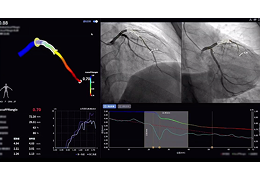

成像智能。

Eclipse 成像智能功能提供强大的处理能力和最佳质量的影像,同时减少质量错误并提高剂量效率。

凭借 AI、专有算法和先进的影像处理能力,提供出色的影像质量和无与伦比的诊断信心。

与标准影像处理相比,智能降噪功能可使客户降低辐射剂量,而不会损失影像质量。这在新生儿和儿科成像中尤其重要,在这种情况下以尽可能低的剂量成像至关重要。

提供相配视图选项,以减少所需的曝光次数,并提供更清晰的感兴趣区域视图。